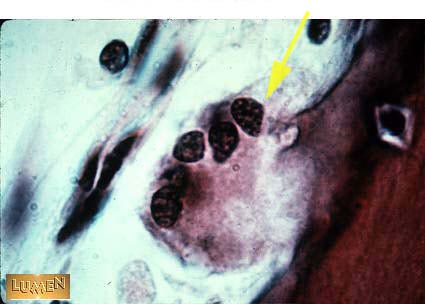

Osteoclast